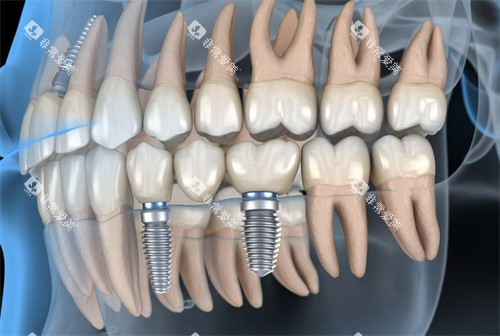

种植牙